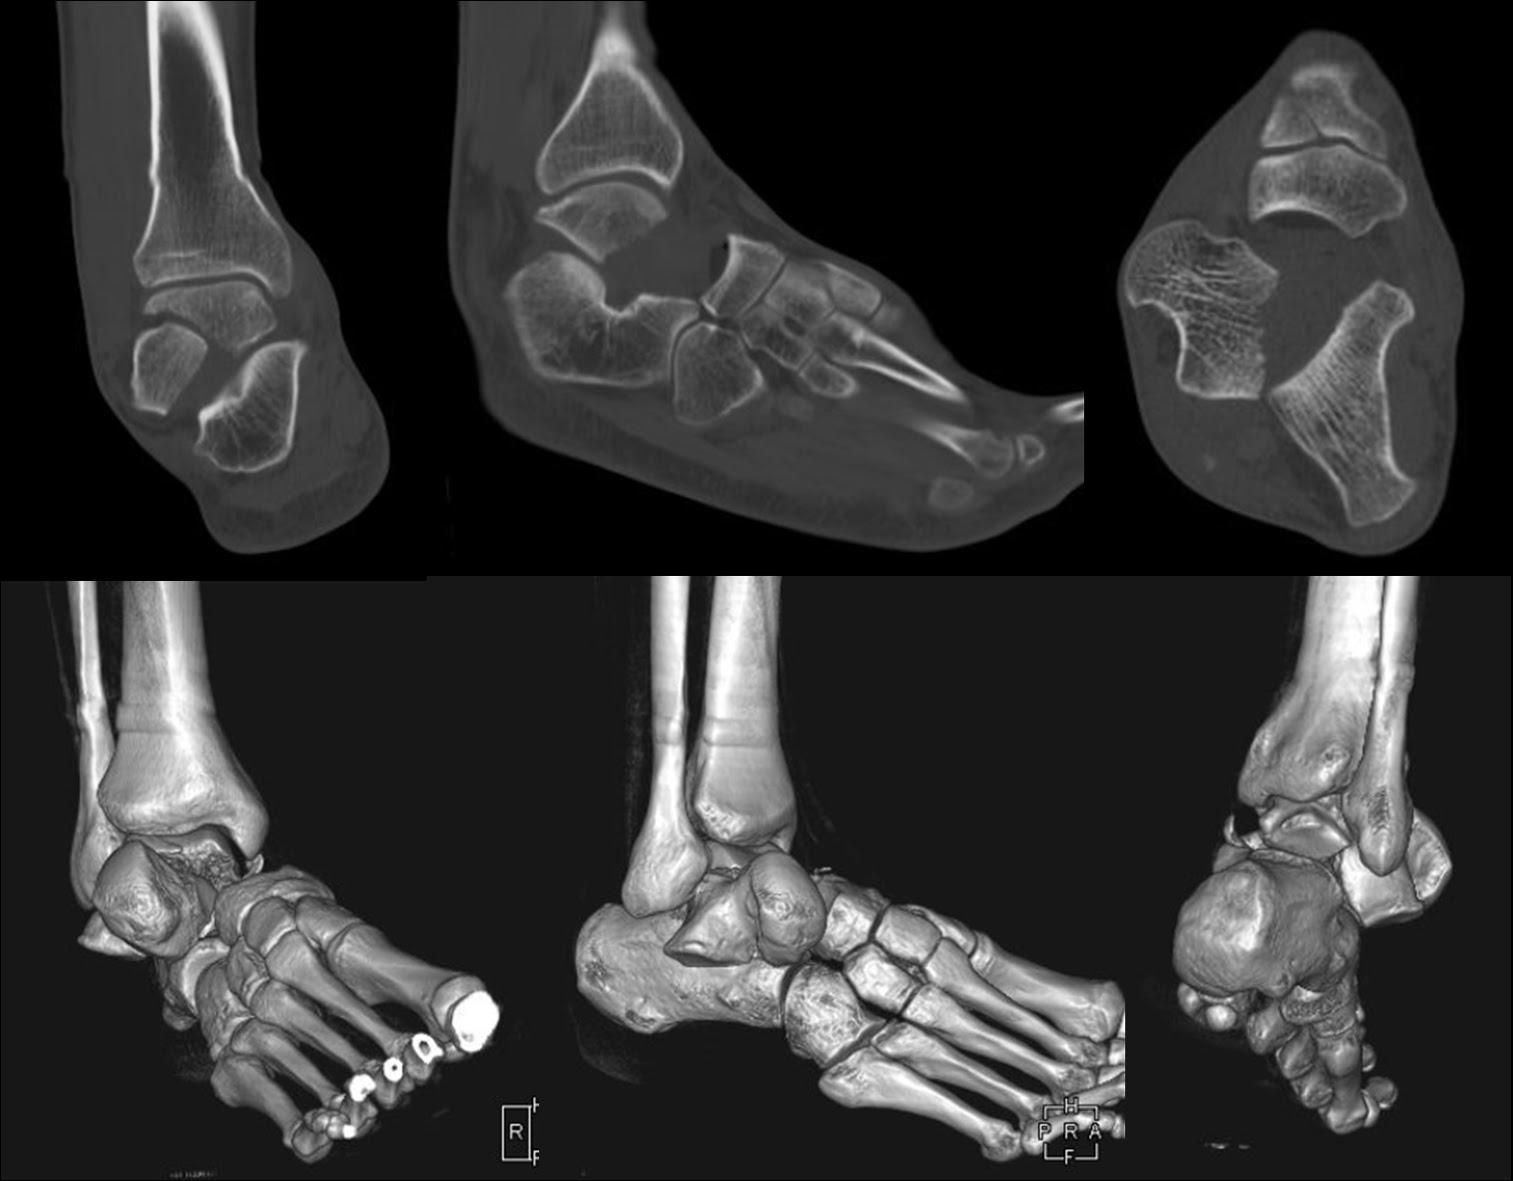

Coronal plane talar body fracture associated with subtalar and Talar Bone Subtalar Joint The american academy of orthopedic surgeons (aaos) describes the subtalar joint as the connection between the heel bone (the calcaneus) and the bone that forms the lower part of the ankle. It occurs at the meeting point of the talus and the calcaneus. The synovial joint known as the st. The calcaneus and talus, two tarsal bones of the foot,. Talar Bone Subtalar Joint.

From faoj.org

Coronal plane talar body fracture associated with subtalar and Talar Bone Subtalar Joint In human anatomy, the subtalar joint, also known as the talocalcaneal joint, is a joint of the foot. Anteriorly, the talar head is located on the anterior and middle facets of the calcaneus, forming the acetabulum pedis with the posterior. It occurs at the meeting point of the talus and the calcaneus. The calcaneus and talus, two tarsal bones of. Talar Bone Subtalar Joint.